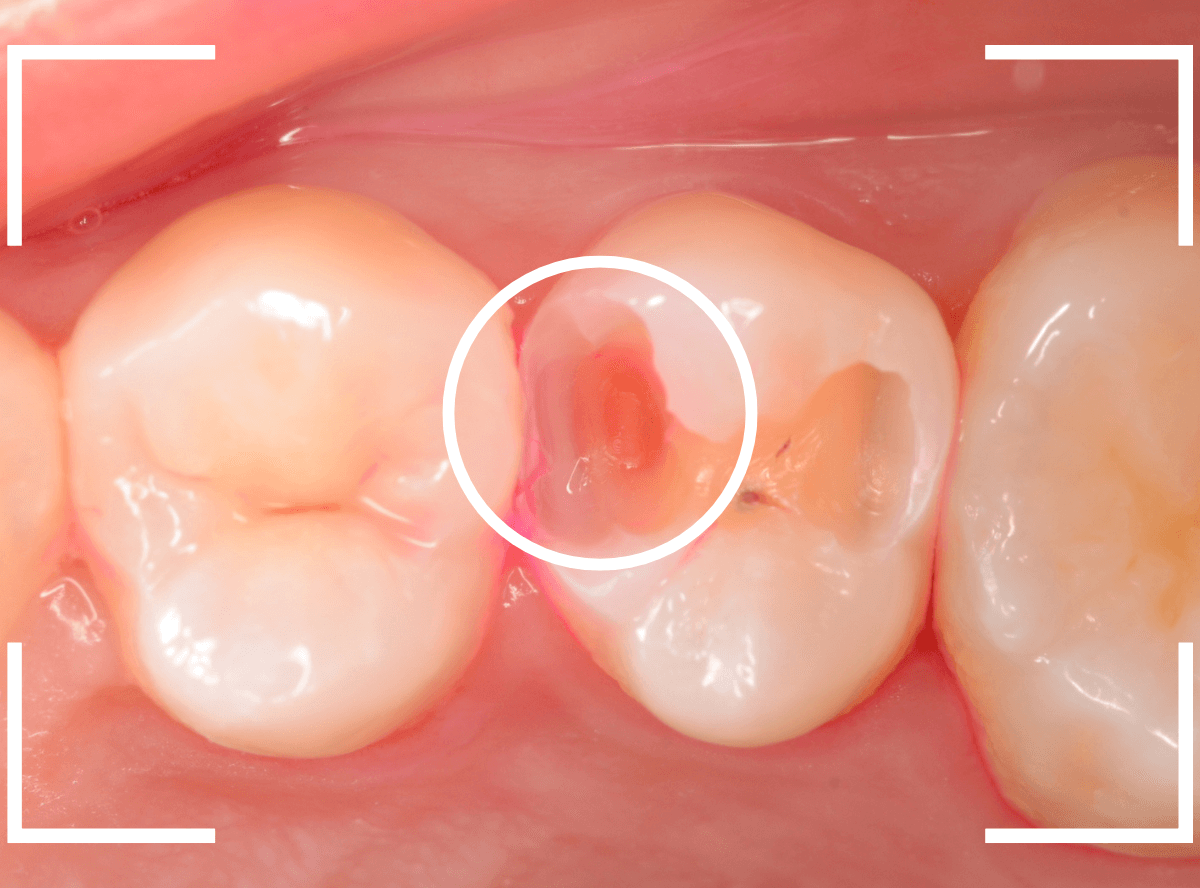

治療を開始します。

先ほどの黒く見えた部分は少し削るとすぐに虫歯が出てきました。

手前の歯まで虫歯を除去した時点で、う蝕検知液で確認します。

赤く染色されている部分が虫歯です。

思ったよりも深めの虫歯ですね。